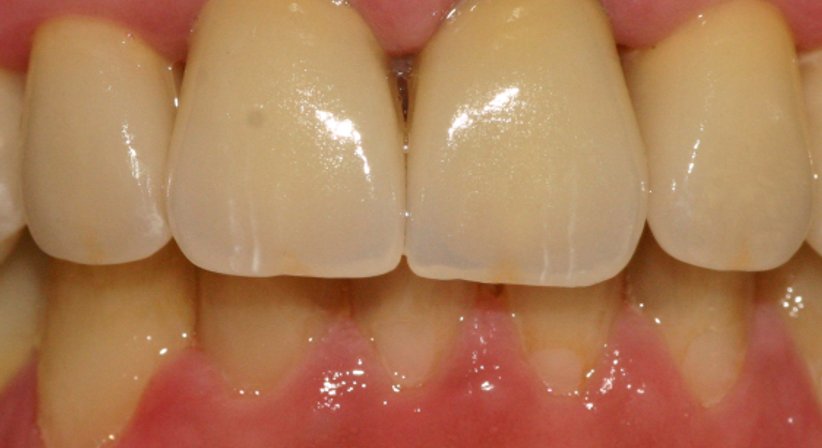

Es gibt unterschiedliche Arten von Zahnkronen, darunter Verblendmetallkronen und Keramikkronen. Zahnkronen aus Keramik haben den Vorteil, dass sie metallfrei sind und als solche mit einer ausgezeichneten Verträglichkeit einhergehen. Dank heutiger Hochleistungskeramiken können Kronen angefertigt werden, welche mit einer ähnlichen Stabilität einhergehen wie Kronen aus Metall, gleichzeitig ist eine Zahnkrone aus Keramik hinsichtlich ihrer Optik weitaus natürlicher und ästhetischer als eine Krone aus Metall (Verblendmetallkronen können unter Umständen im Zahnhalsbereich durch die Schleimhaut schimmern oder im Fall von Zahnfleischrückgang durch einen dunklen Rand sichtbar werden.).

Zu Beginn wird die Karies bzw. die alte Füllung entfernt. Anschließend wird mit einer intraoralen Kamera eine dreidimensionale Aufnahme vom Zahn erstellt, der Patient sitzt hierbei bereits bequem auf dem Behandlungsstuhl - das Abformen, welches einst notwendig war, um einen defekten Zahn zu sanieren entfällt gänzlich. Im nächsten Schritt wird die Zahnrestauration am Bildschirm konstruiert (CAD), anschließend wird die Krone von der Schleifeinheit aus einem Keramikblock gefräst. Die Keramikblöcke sind in vielen verschiedenen Helligkeits- und Farbstufen verfügbar, sodass die Krone nicht nur hinsichtlich ihrer Dimensionen, sondern auch hinsichtlich ihrer Farbe perfekt an den Zahn angepasst werden kann. Nach einer Kontrolle der Passgenauigkeit und einem Glanzbrand wird die Krone zeitnah eingesetzt und ist von da an optisch nicht mehr von den natürlichen Zähnen zu unterscheiden.